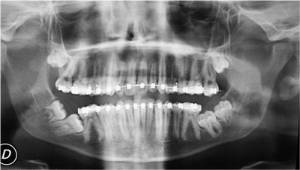

cirugia_bucalcirugia_bucalImplantes dentales, inclusiones dentarias (caninos incluidos y cordales o muelas del juicio), quistes y tumoraciones de los maxilares, boca, cabeza y cuello, cirugía de los tejidos blandos de la boca (làser de CO2), patología y cirugía de las encías (periodoncia), cáncer de la boca, deformidades dentofaciales, traumatismos de la boca y de la cara, patología de las glándulas salivares.

Es una especialidad odontológica que se dedica a la prevención, el diagnostico y el tratamiento de la patología (enfermedades, anomalías y lesiones) de los dientes, de la boca, de los maxilares y de las zonas anexas, que deben tratarse mediante técnicas quirúrgicas. Se trata de problemas que no pueden corregirse sólo con tratamientos conservadores (medicamentos, rehabilitación, etc.) y que deben solucionarse con maniobras quirúrgicas es decir con operaciones que tiene que realizar un dentista especializado en Cirugía Bucal.

Existen muchos tipos de patologías y técnicas que se incluyen en esta especialidad, pero destacaremos algunas de las más importantes y frecuentes:

• Tratamientos de las inclusiones dentarias (extracción de cordales o muelas del juicio, extracción de caninos incluidos, extracción de dientes supernumerarios, etc.).

• Exéresis de quistes y tumores de los maxilares.

• Cirugía periapical (legrado, apicectomía y obturación retrograda).

• Exéresis de lesiones tumorales de la mucosa bucal y de la lengua (épulis, fibromas, papilomas, etc.).

• Cirugía implantológica (colocación de implantes en los maxilares).

• Cirugía periodontal (injertos, regeneración tisular guiada, etc.).

• Cirugía sinusal (elevación del seno maxilar, etc.).

• Cirugía preortodóncica (frenillo bucales, fenestraciones, etc.).